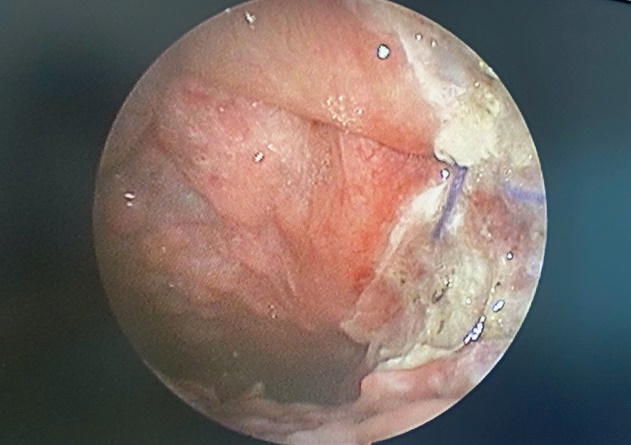

Hốc mổ sau khi cắt khối u và Amidan bên trái bằng dao Ligasure